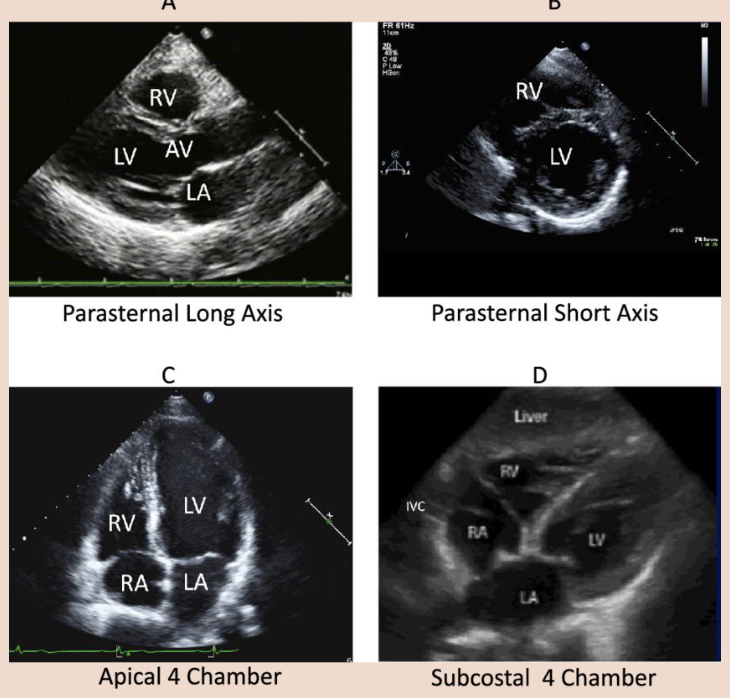

Basic Views in Echo

What is the parasternal long axis view?

The aim in this view is to orientate the beam with the long axis of the left ventricle (LV).

• The transducer is placed to left of the sternum in the 3rd, 4th, or 5th intercostal space with the

transducer indicator orientated towards the right clavicle (approximately 11 o’clock).

• PLAX allows for excellent images of the right ventricle (RV), left atrium, left ventricle, mitral valve, aortic valve, aortic root, aortic outflow tract, and the surrounding pericardium.

What is the parasternal short axis view?

In the PSAX view, the transducer remains in the intercostal space used to obtain the parasternal long axis view and is rotated clockwise 90 degrees so that it is perpendicular to the long axis of the LV (probe marker to left shoulder). It is then tilted to sweep through from base to apex of the heart,

obtaining a number of different views.

• PSAX examine the shapes and sizes of the ventricles. The LV should be bigger than the RV. The LV should be round, and the RV crescent shaped like a reverse letter ‘D’.

What is the Apical 4-Chamber view?

In this view, the transducer is placed at the point of maximum impulse if the patient has a palpable apical beat. Otherwise, it is placed in the fifth intercostal space near the anterior axillary line.

• The beam is directed up towards the patient’s head, and the transducer is rotated so the marker is at around 3 o’clock.

• This view is helpful for the identification of pericardial effusion (fluid between the heart and

pericardium) which indicates cardiac tamponade, as well as RV dilation in pulmonary embolism.

What is a subcostal 4-Chamber view?

This window may provide the only achievable view in technically difficult patients such as those with chronic obstructive pulmonary disease or who are receiving mechanical ventilation.

• The patient is supine and if possible, the knees are slightly bent to reduce abdominal wall tension.

• The transducer is placed below and slightly to the right of the xiphisternum.

• The side marker is in the 3 o’clock position and the transducer is tilted anteriorly. It may be necessary to push slightly downwards into the abdomen in order to achieve this scan plane.

• The subcostal view shows the Inferior Vena Cava (IVC) in a long axis.